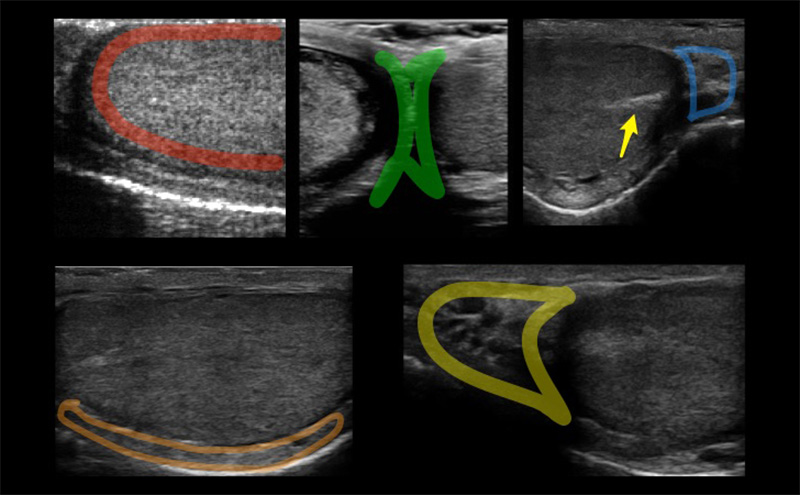

- The normal testis has midgray or medium-level echoes and is homogeneous in appearance. (Figure 3)

Figure 3. Red: Image of the normal testicle with homogenous echotexture. Green: Median raphe. Blue: Tail of the epididymis. Orange: Body of the epididymis. Yellow: Head of the epididymis. Arrow: Mediastinum testis seen as a linear echogenic band

- The epididymis has similar or slightly increased echogenicity as compared to the normal testis.

- The mediastinum testis is seen as a linear echogenic band running parallel to the epididymis, best seen on sagittal view.